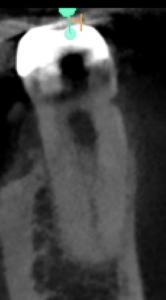

が、術前にCBCTを撮影すればどこに気をつけるべきか?はあらかじめ判断ができる。

術後にPA, CBCTを撮影した。